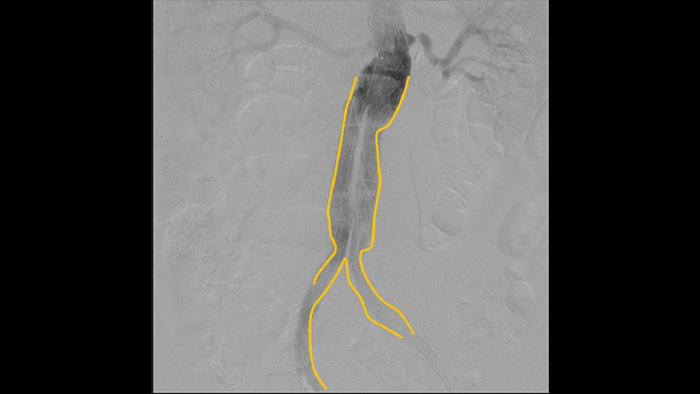

La angiografía por sustracción digital (DSA) se utiliza en procedimientos vasculares intervencionistas para visualizar claramente los vasos sanguíneos mediante la eliminación de estructuras que puedan oscurecer la visibilidad de los vasos. La fluoroscopia Roadmap superpone una imagen de contraste sustraída previamente adquirida en la fluoroscopia en tiempo real, lo que le permite rastrear un dispositivo sin volver a inyectar el contraste.

Utilice la herramienta de creación de contornos para marcar fácilmente una bifurcación o rama lateral simplemente dibujando en el monitor de la estación de visualización móvil con el dedo o un ratón conectado externamente.